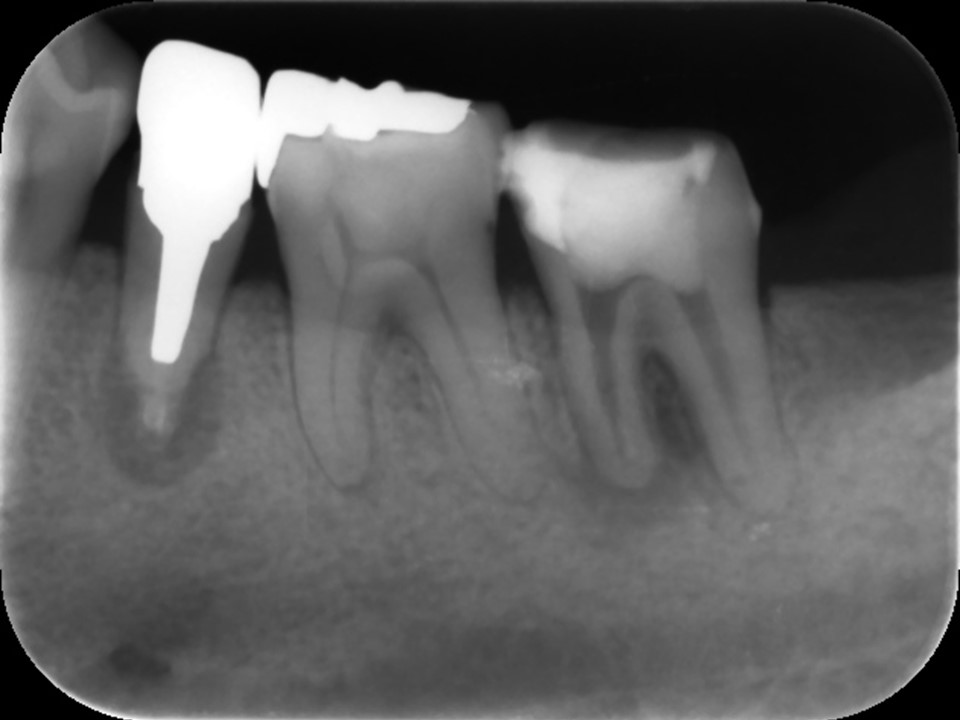

![]() |

図1、根管治療が不十分で白い薬が根尖(歯根の先端)まで届いておらず、根尖部に歯槽骨の吸収による黒いレントゲン透過像を認める。我が国の保険の根管治療はこのような例が非常に多いです。

図2、根尖部まで隙間なく緊密に薬が詰まっているのが分かる。正しく根管治療を行えば、溶けて吸収した歯槽骨は数か月程度で再生してきます。